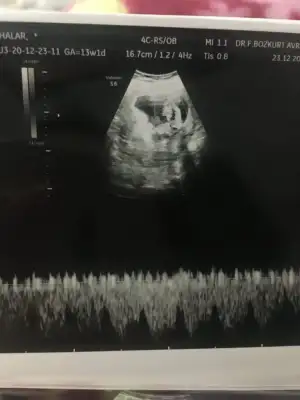

Merhabalar biraz büyüdük tekrar geldik 12+2 karından bakıldı bi tahmininiz varmı 😊

Eklentiler

• IMG_20201223_095839.webp

IMG_20201223_095839.webp

41,1 KB · Görüntüleme: 56